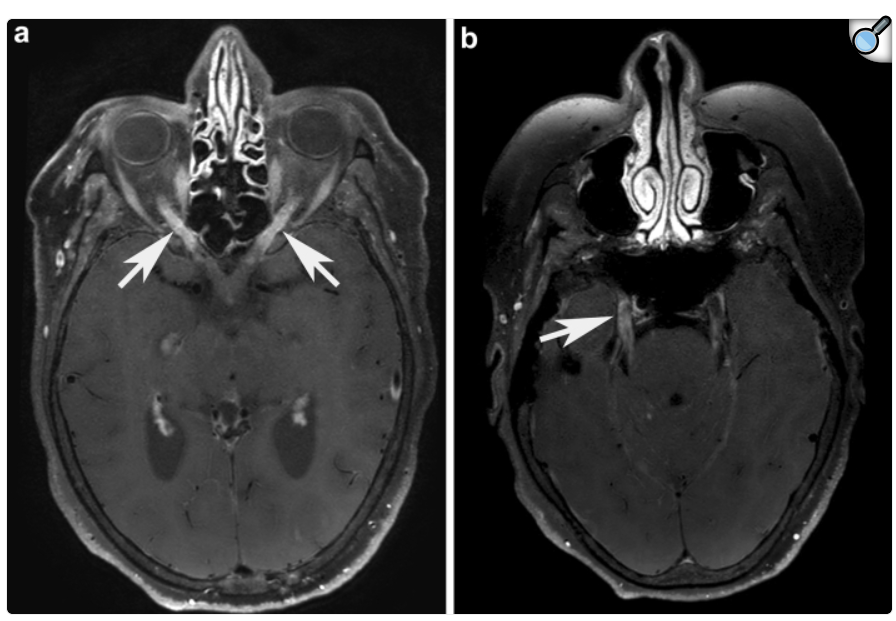

Astrocitopatía Glial Fibrilar